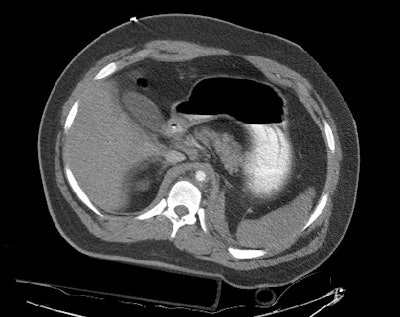

A CT scan of the chest demonstrated a large mediastinal hematoma (yellow arrows) and a left pleural fluid collection that was subsequently found to be a hemothorax. There was irregularity to the aortic arch near the isthmus (black arrow) which is highly suspicious for an aortic laceration, however, images at the level of the diaphragmatic hiatus demonstrated a more impressive finding (below).

CT images more inferiorly revealed an intimal flap and marked irregularity to the contour of the aorta consistent with traumatic injury (black arrows). Slightly below this level there was a near complete lack of opacification of the vessel (lower image).